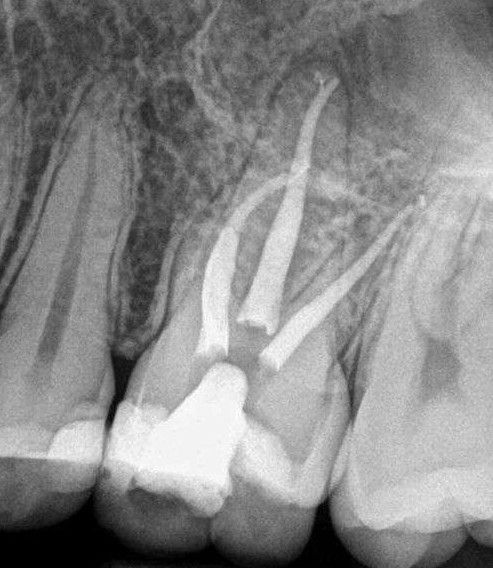

Root canal treatment is a dental procedure used to save a tooth with an inflamed or infected pulp. The pulp, located inside the tooth, contains nerves and blood vessels that can become damaged due to deep decay, cracks, trauma or repeated dental work. The procedure involves carefully removing the damaged tissue, cleaning and disinfecting the inner canals and sealing them to prevent further infection. Root canal treatment helps retain the natural tooth, maintaining its function and potentially avoiding the need for extraction.

During a root canal, the dentist begins by numbing the area to help ensure comfort. An opening is made in the tooth to access the pulp chamber and root canals. The infected or inflamed pulp is removed, and the canals are cleaned and shaped. After disinfection, the canals are filled with a biocompatible material and sealed to help prevent reinfection. In most cases, the procedure is completed over one or more visits, depending on the tooth’s condition and complexity.

Visit 2: The chamber and root canals are cleaned and slightly enlarged, and medication is placed in the canal and sealed for a period of time.

Visit 3: The canals are sealed with a rubbery filling material and the tooth is then restored.